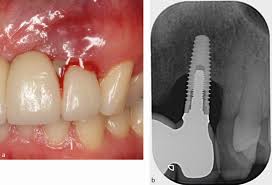

ایمپلنت دندان یکی از پیشرفته‌ترین روش‌های جایگزینی دندان است.

در این روش، یک پایه فلزی از جنس تیتانیوم یا زیرکونیا در استخوان فک قرار داده می‌شود.

این پایه پس از مدتی با استخوان فک جوش می‌خورد، فرآیندی که به آن اُستئواینتگریشن گفته می‌شود.

پس از تثبیت پایه، تاج دندان مصنوعی روی آن نصب می‌شود و عملکردی مشابه دندان طبیعی دارد.

ایمپلنت‌ها به دلیل شباهت زیاد به دندان واقعی و دوام بالا، محبوبیت زیادی در میان بیماران و دندانپزشکان دارند.

فالوآپ های بعد درمان ایمپلنت

این معاینات جهت رد هر گونه عارضه همانند پری ایمپلنتایتیس می باشد.

تصویری از دندان<yoastmark class=

در جلسات فالوآپ ،صرفا از گرافی های PAساده با زاویه جهت بررسی مشکلات احتمالی استفاده می شود.علاوه بر این دندانپزشک با استفاده از پروب و سوند هر گونه پاکت لثه ای و لقی را در جهت رد پری ایمپلنتایتیس شناسایی می کند.به صورت کلی مقداری تحلیل استخوان در هر سال طبیعی می باشد . اما تحلیل های بیشتر و نگران کننده باید بررسی شوند .